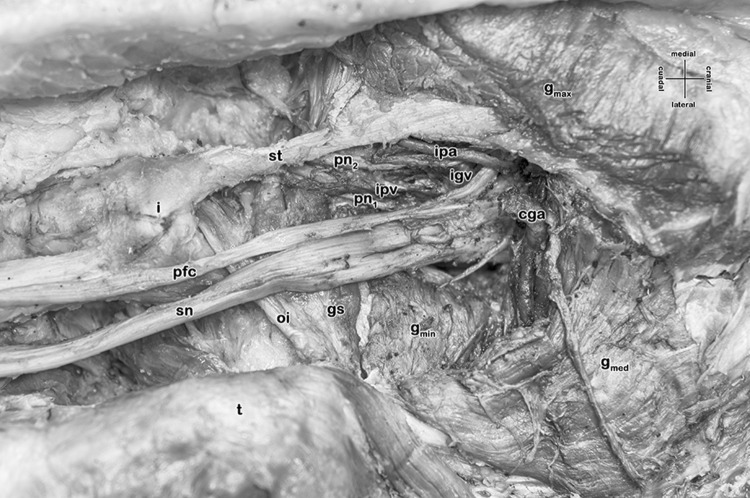

The greater sciatic foramen is properly formed by the greater sciatic notch, the sacrotuberal and the sacrospinal ligaments. Only neurovascular structures pass, a common gluteal artery (replacing the superior gluteal artery), a superior gluteal vein, the sciatic nerve, an inferior gluteal vein, a (bipartite) pudendal nerve and the internal pudendal vessels. In other words, the piriformis muscle is missing as well as the inferior gluteal artery. Both, a vessel resembling the ‘descending branch of the inferior gluteal artery’ and the artery to the sciatic nerve originate from the common gluteal artery. Furthermore, at the lesser sciatic foramen, a quite large gemellus superior muscle accompanies the obturator internus muscle, whereas the gemellus inferior muscle is also missing (Fig. 1).

Fig. 1.

Right deep gluteal region with absent piriformis muscle (female, 60 years)

Abbreviations

- gi

Gemellus inferior muscle

- gs

Gemellus superior muscle

- tgmax

Gluteus maximus muscle

- gmed

Gluteus medius muscle

- gmin

Gluteus minimus muscle

- igv

Inferior gluteal vein

- ipa

Internal pudendal artery

- ipv

Internal pudendal vein

- oi

Obturator internus muscle

- pm

Piriformis muscle

- pfc

Posterior femoral cutaneous nerve

- pn1, pn2

Doubled pudendal nerve

- st

Sacrotuberal ligament

- sn

Sciatic nerve

- cga

Common gluteal artery

- sgv

Superior gluteal vein

- t

Greater trochanter

- i

Ischial tuberosity